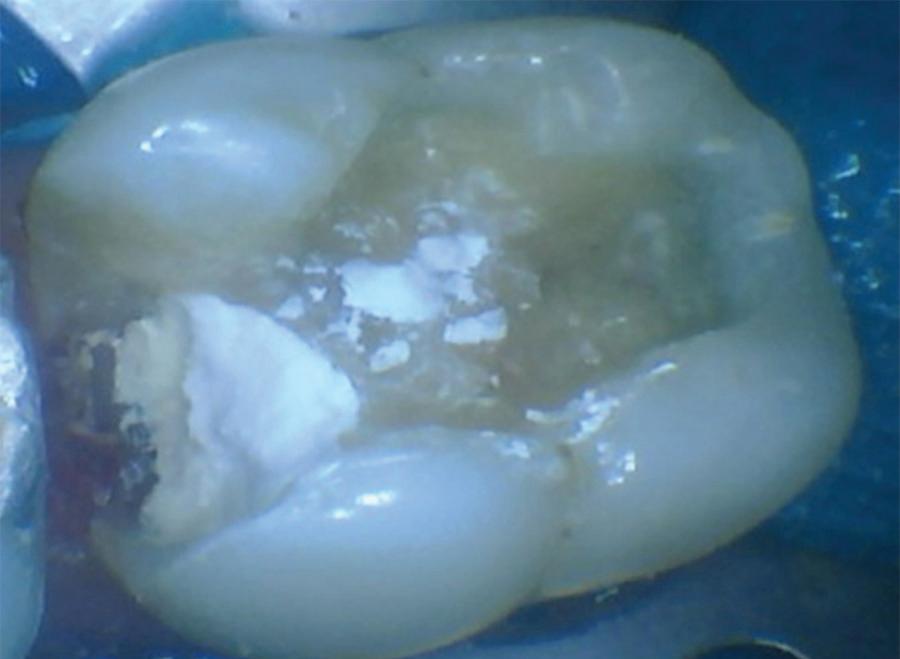

In the endodontic stage, conservative endodontic preparation and obturation with modern techniques are performed as they are for any tooth. All endodontic procedures are performed under an operating microscope to maximize visualization and illumination of the fracture line (Fig 1). The coronal portion of the newly placed gutta percha is removed 2 to 3 mm below the deepest extent of the crack in the affected canal to prepare for intraradicular barrier placement (Fig 2). Gutta percha is also removed 2 to 3 mm into the other noncracked canal orifices in the tooth to prepare for traditional orifice barriers. Microscopic transillumination with a fiber-optic light, in which an LED light probe is placed against buccal or lingual tissues overlying the roots, is utilized to illuminate the root and enhance visualization of the crack (Fig 3). A flowable resin-modified glassionomer or composite resin is then placed in this newly created void from the level of the gutta percha to the floor of the pulp chamber in all canal orifices (Fig 4). A composite resin core is then placed to permanently restore the endodontic access. If a temporary or permanent crown is not placed immediately after the endodontic procedures, the tooth is reduced

Fig 1. Microscopic visualization of the radicular extension of the crack (arrows) entering the canal.

Fig 4.

Fig 3. Microscopic transillumination. A. Canal space viewed under microscopy without transillumination. B, C. Same canal viewed at different angles with the aid of a fiber-optic light. Transillumination reveals a root fracture.

Fig 2. Gutta percha removed 2 mm apical to the terminus of the fracture (arrows).